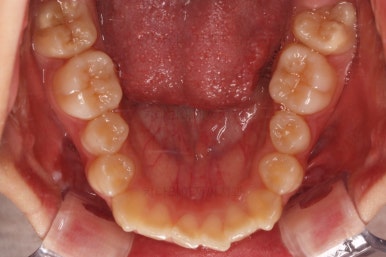

연산동치과 초진 시, 입안의 모습입니다.

보시다시피 앞니쪽이 많이 삐뚤고요. 어금니쪽이 긴밀하지 못한 부정교합이 있네요.

그리고 왼쪽 하단의 사진에 화살표를 보시면, 예전에 신경치료를 해둔 치아인데 어린 나이에 신경치료를 하다보니 크라운으로 치료를 마무리 하지 못했어요.